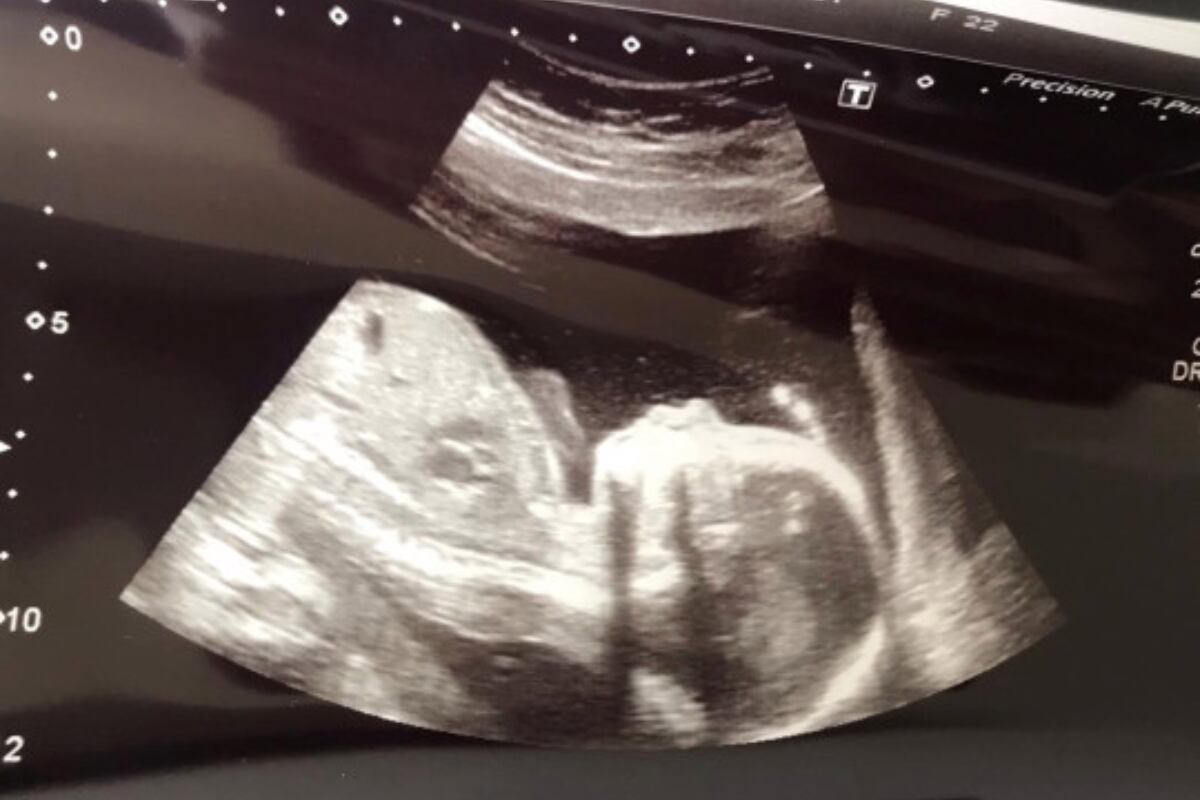

Pero la sorpresa trascendió a esta brusca acción, pues tras ser atendida se enteró que se encuentra en la dulce espera, exactamente con cuatro semanas, sin que ella tuviera la más mínima idea de la gestación.

Sabiendo de su nueva situación, Beth mostró preocupación por la salud de su bebé, sobre todo para conocer si había algún problema luego de la fuerte jugada, pero para su alivio las pruebas no detectaron problema alguno.

“Al principio fue preocupante saber que estaba embarazada durante el partido. Llamé al médico y me dijeron que todo estaba bien (…) No se puede hacer un escaneo hasta las seis semanas, por lo que tuve que esperar dos más”, dijo la futura madre.